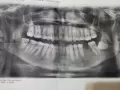

Беспокоит периодическая тянущая боль слева (от зубов к носу). Можно ли по снимку определить причину?

• Внимательно изучил снимок, но стоматологических причин не увидел. Надо тщательно прощупать переходную складку слева и проекции верхушек корней. Затем, если выявится где-то болезненность, сделать прицельный снимок для лучшей четкости.